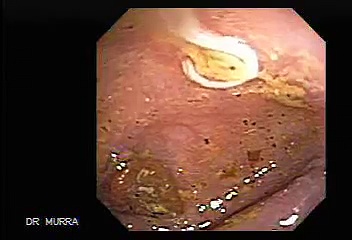

April 24, 2025Video Colonoscopy Showing a Parasite in the Cecum